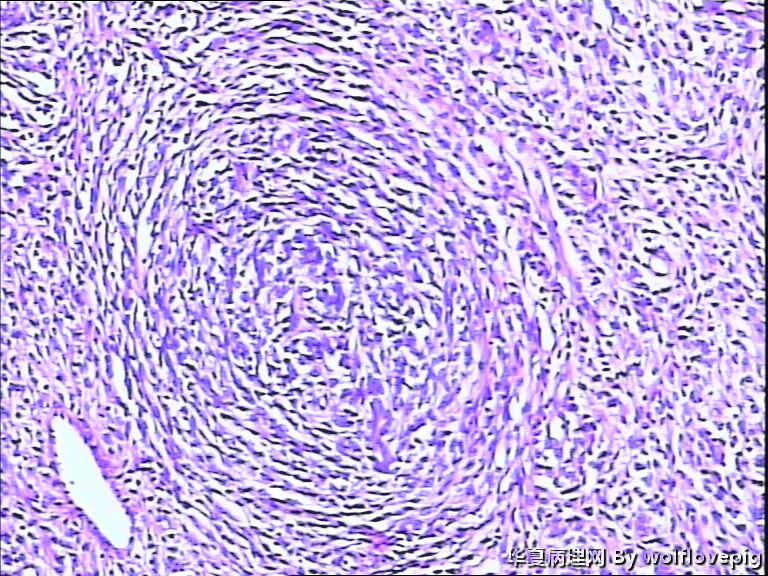

37y,肌壁间可见多个小结节0.2~0.8cm。

图1